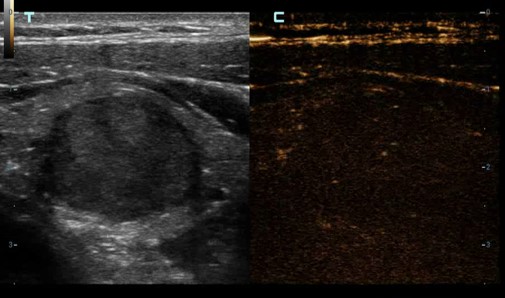

Kontrastné zobrazovanie - UWN+ Kontrastné zobrazovanie: Ultraširokopásmové nelineárne plus kontrastné zobrazovanie

UWN+ (Ultra-Wideband Non-linear) kontrastné zobrazenie - CEUS: Excelentná citlivosť na kontrastnú látku aj s minimálnym signálom. Dlhší perfúzny čas s nižším MI. Lepšia vizualizácia perfúzie v jemných cievach s MFE ( Micro Flow Enhancement ). Presná diagnostika benígnych a malígnych tumorov. Výrazne zvyšuje mieru detekcie drobných lézií.

UWN+ (Ultra-Wideband Non-linear) kontrastné zobrazenie - CEUS: Excelentná citlivosť na kontrastnú látku aj s minimálnym signálom. Dlhší perfúzny čas s nižším MI. Lepšia vizualizácia perfúzie v jemných cievach s MFE ( Micro Flow Enhancement ). Presná diagnostika benígnych a malígnych tumorov. Výrazne zvyšuje mieru detekcie drobných lézií.

UWN+ (Ultra-Wideband Non-linear) kontrastné zobrazenie - CEUS: Excelentná citlivosť na kontrastnú látku aj s minimálnym signálom. Dlhší perfúzny čas s nižším MI. Lepšia vizualizácia perfúzie v jemných cievach s MFE ( Micro Flow Enhancement ). Presná diagnostika benígnych a malígnych tumorov. Výrazne zvyšuje mieru detekcie drobných lézií.

UWN+ (Ultra-Wideband Non-linear) kontrastné zobrazenie - CEUS: Excelentná citlivosť na kontrastnú látku aj s minimálnym signálom. Dlhší perfúzny čas s nižším MI. Lepšia vizualizácia perfúzie v jemných cievach s MFE ( Micro Flow Enhancement ). Presná diagnostika benígnych a malígnych tumorov. Výrazne zvyšuje mieru detekcie drobných lézií.

Kontrastné zobrazovanie - UWN+ Kontrastné zobrazovanie: Ultraširokopásmové nelineárne plus kontrastné zobrazovanie